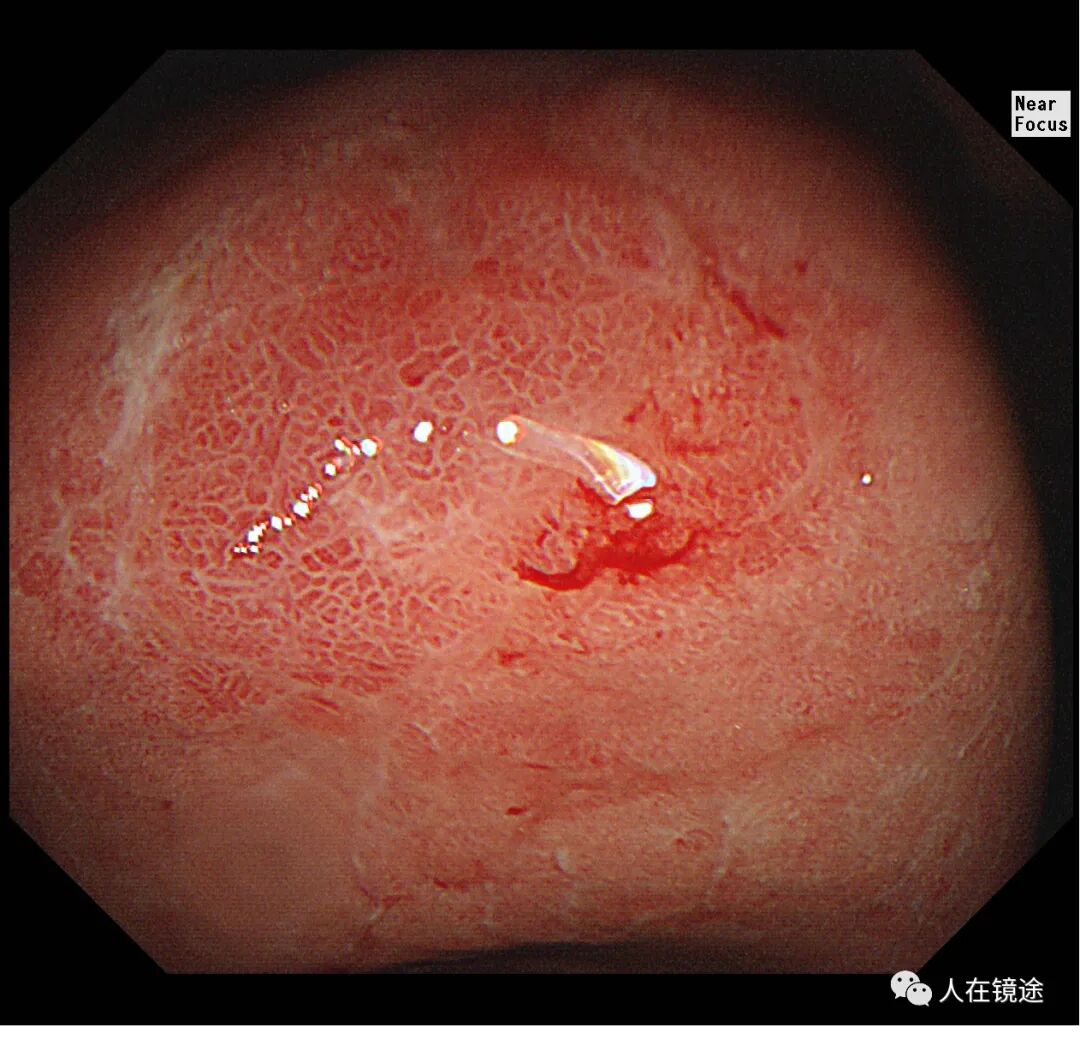

白光+近焦示:胃窦小弯见一0.8*1.2cmIIa粘膜发红病变,微结构稍紊乱,表面粘膜高低不平伴自发性出血。